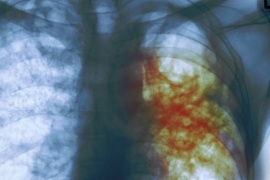

La Organización Mundial de la Salud ( OMS ) ha hecho públicas nuevas orientaciones para mejorar el tratamiento de la tuberculosis multirresistente, para la que recomienda tratamientos exclusivamente orales, que son más eficaces y tienen menos probabilidades de producir efectos colaterales  adversos. Conocé la situación en nuestra provincia

La tuberculosis es una de las 10 principales causas de mortalidad en el mundo.

La tuberculosis es la enfermedad infecciosa que más muertes produce. Cada día se cobra 4500 vidas. La carga más pesada la soportan las comunidades con problemas socioeconómicos, quienes trabajan y viven en entornos de alto riesgo y los más pobres y marginados.